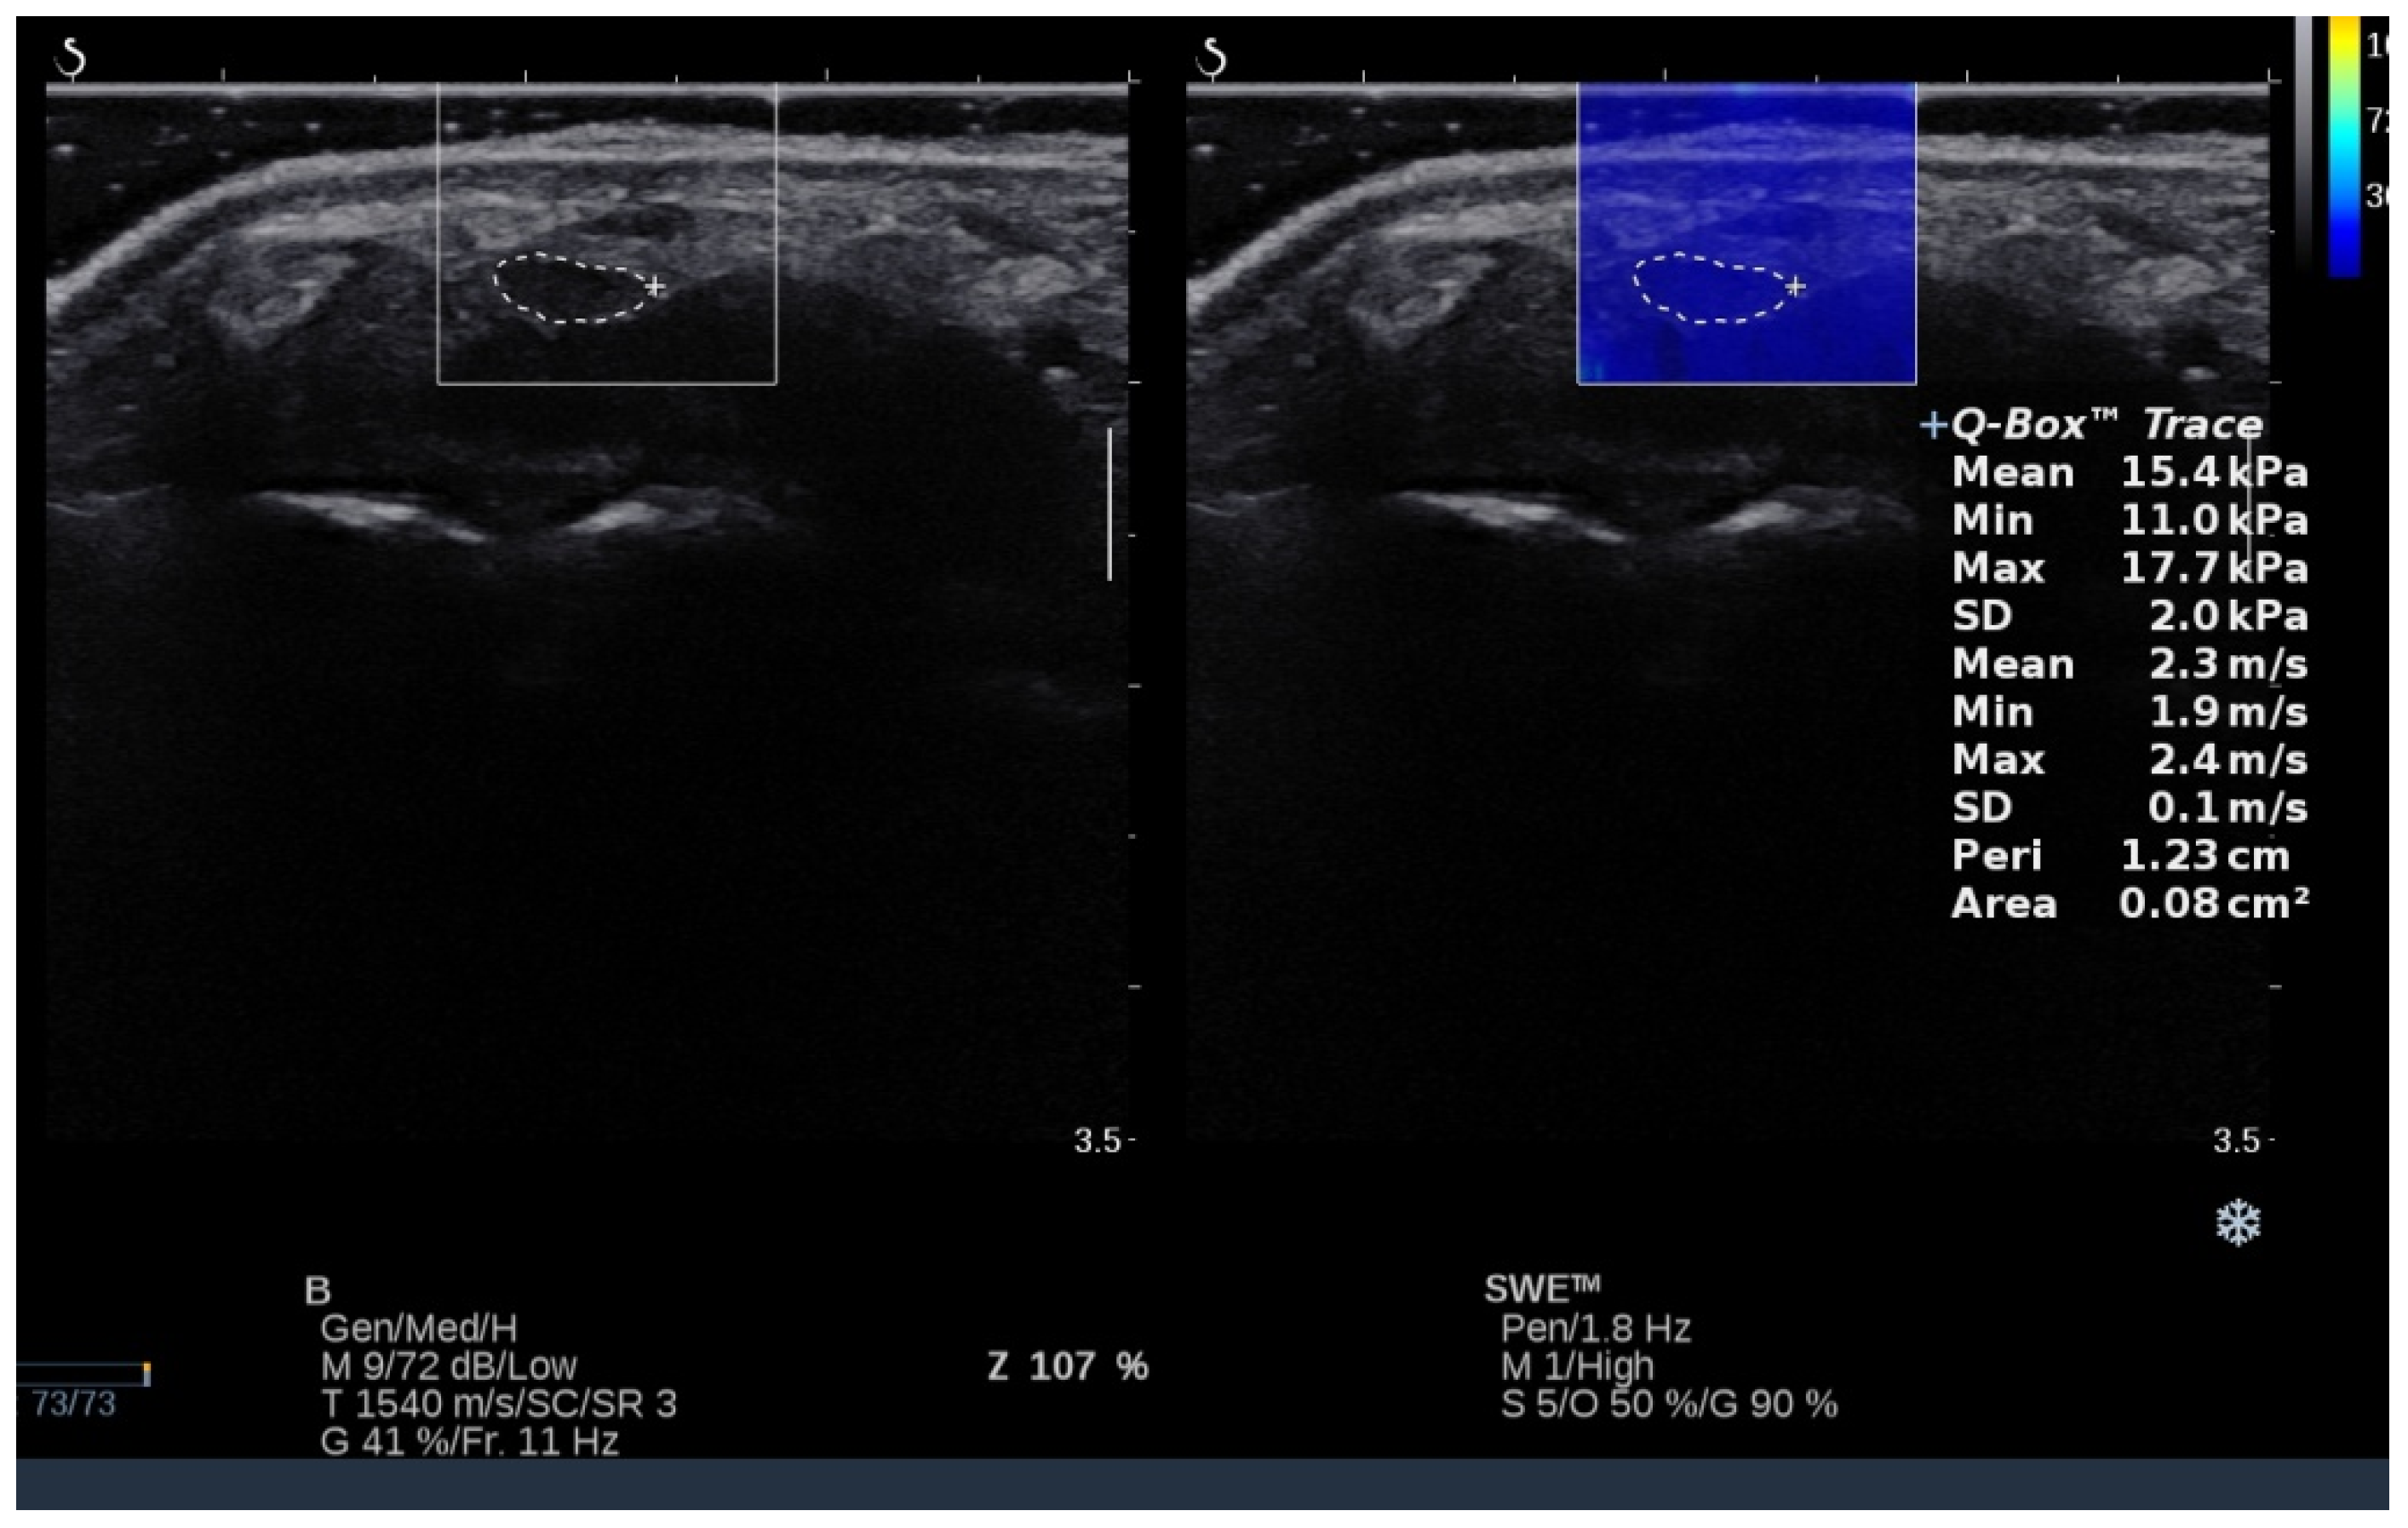

2.3. Ultrasound Measurements

3.3. Shear Modulus